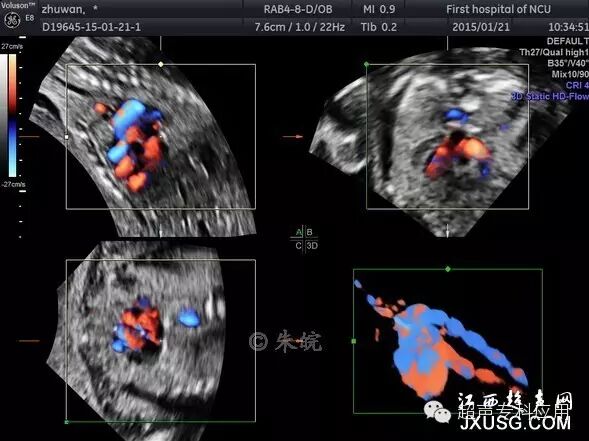

1.8 胎儿心脏时间空间成像(spatiotemporal image correlation,STIC) 这是动态的心脏三维超声成像,通过这一技术,可以获得心脏任何方向的动态切面、心脏大血管动态立体结构,观察心脏结构及畸形状态。

胎儿心脏血管三维成像

胎儿心脏彩色STIC成像